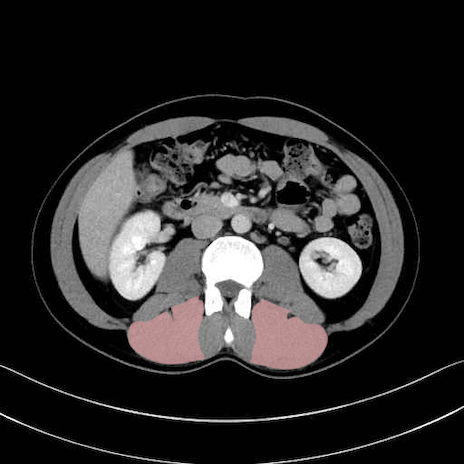

脊柱起立筋 (Erector spinae)

多裂筋 (Multifidus)